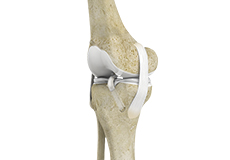

High Tibial Osteotomy

High tibial osteotomy is a surgical procedure performed to relieve pressure on the damaged site of an arthritic knee joint. It is usually performed in arthritic conditions affecting only one side of your knee and the aim is to take pressure off the damaged area and shift it to the other side of your knee with healthy cartilage.